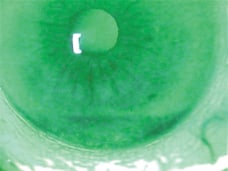

The patient presented with lid margin telangiectasia (above) and meibomian gland inflammation.